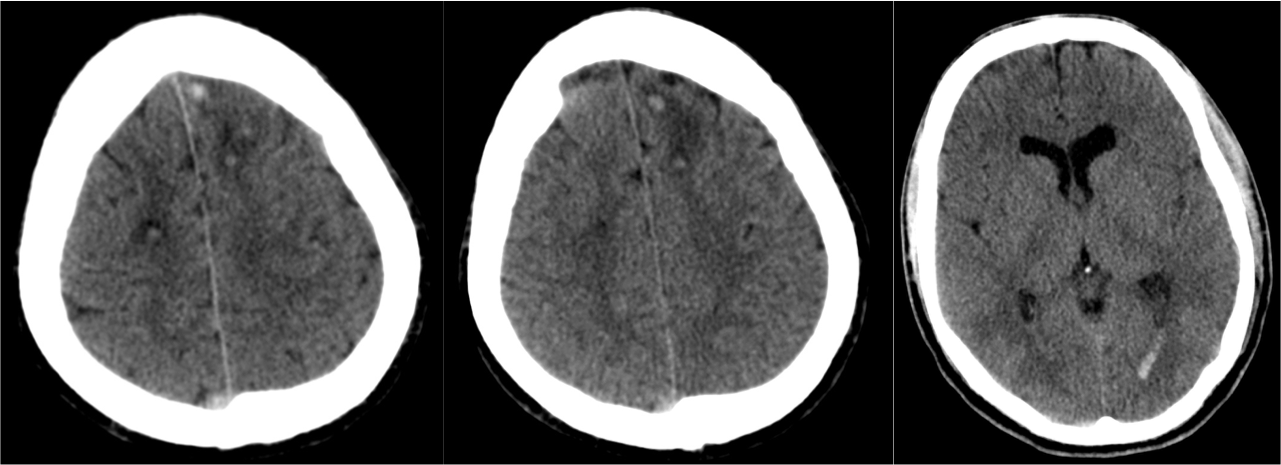

Hallazgos TC:

- En fase aguda puede ser Nomal.

- Edema cerebral (borramiento de surcos)

- Focos hemorrágicos en las sitios anteriomente descritos

- En fase cronica = zonas hipodensas + atrofia.

1- Edema cerebral difuso: Aparece en las primeras 48 horas del traumatismo. Se identifica por:

- Produce efecto de masa.

- Borramiento de surcos = pérdida de la interfase sustancia gris-sustancia blanca.

- Otros: signo del cerebelo blanco, falsa hemorragia subaracnoidea…